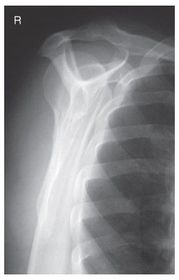

Which projection/position is this? Transthoracic Shoulder ___________________ ribs are blurred out from orthostatic breathing